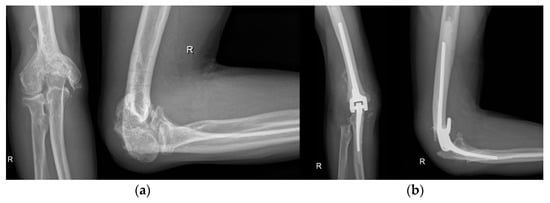

4.4. Wrist and Hand

- Martinez-Catalan, N.; Sanchez-Sotelo, J. Primary Elbow Osteoarthritis: Evaluation and Management. J. Clin. Orthop. Trauma 2021, 19, 67–74. [Google Scholar] [CrossRef]

- Kwak, J.-M.; Jeon, I.-H. Surgical Management for Primary Osteoarthritis of the Elbow. J. Orthop. Surg. Hong Kong 2021, 29, 2309499020988174. [Google Scholar] [CrossRef]

- Karuppaiah, K. Is There a Role for Elbow Arthrodesis in 21st Century—Current Concepts and Overview of Surgical Techniques. J. Clin. Orthop. Trauma 2021, 20, 101466. [Google Scholar] [CrossRef]